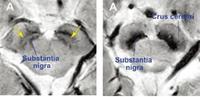

ºÐ´ç¼¿ï´ëº´¿ø ¿¬±¸ÆÀ, ÆÄŲ½¼º´ Áø´Ü ¿µ»ó ¹ÙÀÌ¿À¸¶Ä¿..

ÃÖ±Ù ±¹³» ¿¬±¸ÁøÀÌ ÆÄŲ½¼º´ ¹× ÆÄŲ½¼ ÁõÈıº¿¡¼ÀÇ ³ú ÀÚ±â°ø¸í¿µ»ó(MRI)ÀÇ ÃֽŠÁö°ßÀ» Áý´ë¼ºÇÑ ¸®ºä ³í¹®(Á¾¼³)À» ¹ßÇ¥ÇØ °ü½ÉÀ» ¸ðÀ¸°í ÀÖ´Ù. ¸®ºä ³í¹®Àº ÇØ´ç ºÐ¾ß ÃÖ°í Àü¹®°¡µéÀÌ ÃֽŠ¿¬±¸ ¼º°ú¿Í °á°ú¸¦..